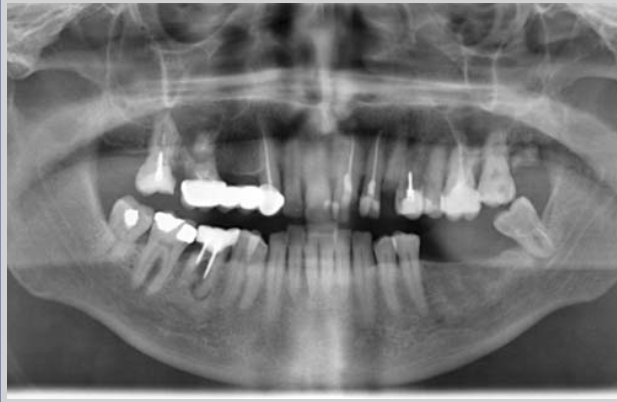

Рисунок 2 - Рентгенограмма, характеризующая у больных воспалительный процесс в тканях пародонта